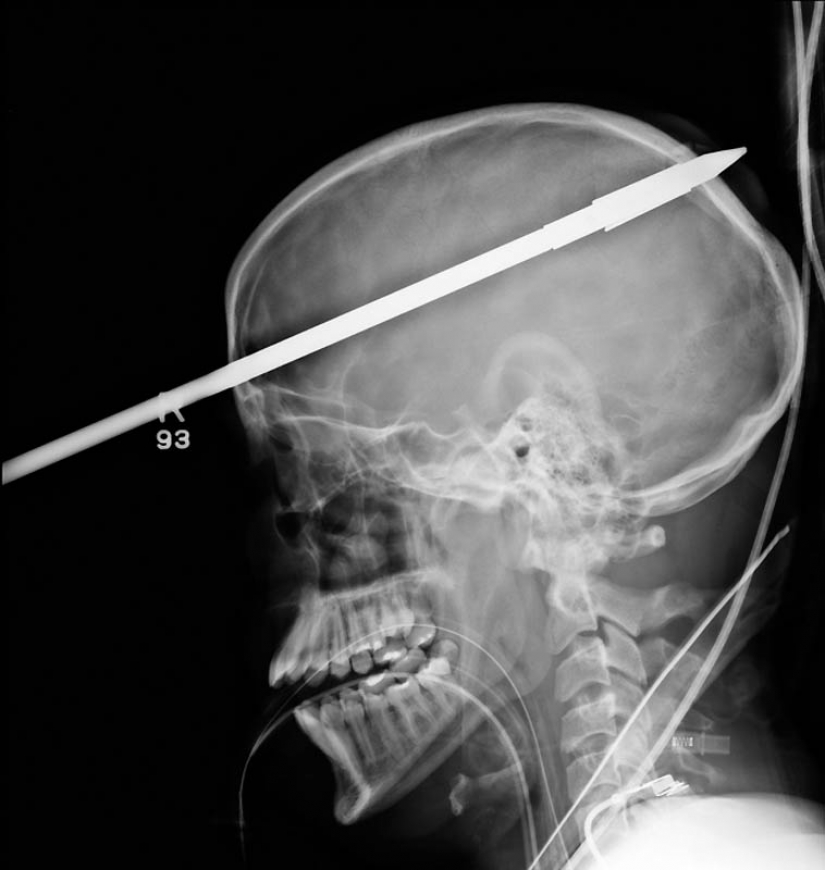

11. The spear from the harpoon, caught in the head of a 16-year-old boy fishing.